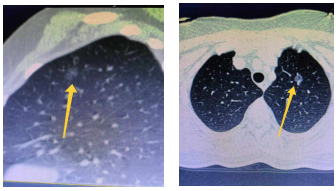

随着健康体检的普及及人们健康意识的提高,越来越多的人在健康查体中查出肺部结节,其中部分患者两侧肺都会有高度疑似早期肺癌的肺结节,传统方案通常是先对病情较严重的一侧肺部手术治疗,待恢复二到三个月后再考虑进行另一侧手术,这对患者无论在身体和心理都带来不小的负担。

我院胸外科全年手术例数全省领先,在先进技术的应用上具有绝对优势。针对双侧肺结节患者,可在胸腔镜下一管双做、同期切除,已成功开展多例,手术创伤小、术后效果好,避免了患者经受二次手术的痛苦和煎熬。

近日,胸外科王述波主任先后为两例患者实施了一管双做早期肺癌根除术,患者一男一女,年龄均40岁出头,体检时发现两肺都有结节,考虑为双侧早期肺癌。因患者为家庭中流砥柱,上有老下有小,这样的查体结果无疑晴天霹雳,心理压力极大。

患者基于对我院胸外科的了解和信任,先后找到王述波主任并充分表达了自己的积极治疗意愿,希望能一次性手术并以最小的创伤同时解决两侧肺结节问题。虽然这样的手术难度大,对手术医师的技术要求较高,是否能同时根除双肺结节,取决于第一侧手术的效果,因为手术过程中,在对一侧肺部手术时患者仅可通过另一侧肺部通气,而且两肺同期经受手术创伤会增加术后发生呼吸功能不全的风险,但王主任对患者身体做了全面评估后,决定实施一管双做手术方案。王述波主任在手术过程中严密观察各项指标,顺利地完成了患者的心愿,一次性切除了患者双侧结节。

王述波主任团队突破传统理念,运用胸腔镜技术一次手术完成两侧早期肺癌根治术,实现了一种新的早期肺癌治疗思路。胸腔镜技术能更大限度减少患者创伤,解剖性肺段切除达到根治两侧早期肺癌的目的,既减少了手术次数,又有效缩短了患者恢复的时间,患者可在一周内恢复出院。